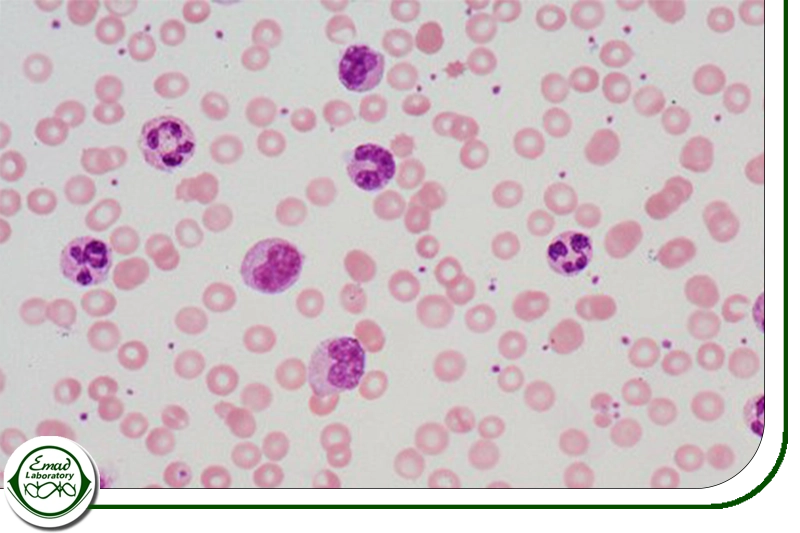

گلبول های سفید خون یا لکوسیت ها سلول هایی هستند که جزو سیستم ایمنی بدن محسوب می شوند و به محافظت بدن در برابر بیماری ها و عوامل بیماری زا کمک می کنند. همه گلبول های سفید از سلول های بنیادی خاصی در مغز استخوان به نام سلول های بنیادی خونساز ساخته می شوند. این سلول ها در نقاط مختلف بدن مثل خون و سیستم لنفاوی حضور دارند. انواع مختلف گلبول های سفید شامل گرانولوسیت ها مثل نوتروفیل ها، ائوزینوفیل ها و بازوفیل ها، مونوسیت ها و لنفوسیت ها شامل سلول های T و سلول های B می باشد.

یکی از ویژگی های مهم گلبول های سفید این است که آن ها هسته دارند، برخلاف گلبول های قرمز که هسته ندارند. گلبول های سفید به دو دسته اصلی تقسیم می شوند: سلول های میلوئیدی و سلول های لنفوئیدی. سلول های میلوئیدی شامل نوتروفیل ها، ائوزینوفیل ها، بازوفیل ها، ماست سل ها و مونوسیت ها هستند. مونوسیت ها می توانند به سلول های دندریتیک و ماکروفاژ تبدیل شوند و برخی از این سلول ها توانایی بلعیدن میکروب ها و ذرات خارجی را دارند. سلول های لنفوئیدی شامل انواع مختلفی از سلول های T و B هستند که هر کدام نقش خاصی در سیستم ایمنی دارند، مثل کمک کردن به دیگر سلول ها یا تولید آنتی بادی.

گلبول های سفید در مغز استخوان تولید می شوند و وظیفه شان دفاع از بدن در برابر بیماری ها است. اندازه گیری تعداد گلبول های سفید یکی از بخش های مهم آزمایش خون است. وقتی تعداد گلبول های سفید در خون بیشتر از حد طبیعی شود، معمولاً نشانه وجود عفونت یا التهاب در بدن است. در برخی موارد هم ممکن است نشان دهنده بیماری های خاصی مثل سرطان خون یا مشکلات مغز استخوان باشد. گلبول های سفید تقریباً یک درصد از حجم کل خون را تشکیل می دهند و تعدادشان کمتر از گلبول های قرمز است. گلبول های سفید شامل چندین نوع مختلف هستند که هر کدام نقش خاصی در دفاع بدن ایفا می کنند. انواع اصلی گلبول های سفید عبارتند از: